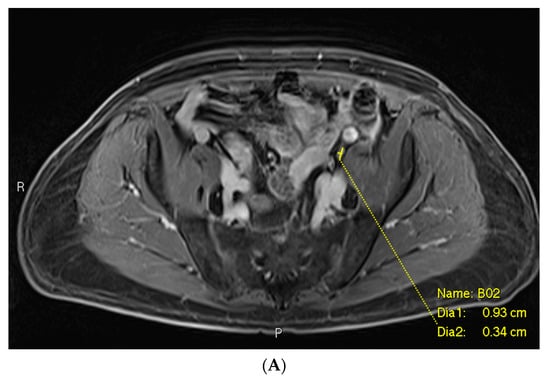

3.1. Example 1—Anatomically Normal Lymph Node Metastasis

As seen in Figure 3, the largest class, comprising half of the cases, was anatomically normal. In other words, the size and morphology of the metastatic focus did not suggest an abnormality on MRI. This description applied to many false negative cases involving lymph node metastases. In this case, the initial mpMRI was negative for the lymph node metastases by size criteria, while the PSMA PET showed a PSMA-avid, subcentimeter, left-sided lesion (Figure 3C). Detailed review of the mpMRI confirmed that the lymph node in question measured well under 1.0 cm in short axis, with a similar “cold” contralateral lymph node with essentially the same characteristics (Figure 3A,B). There were no other features in the mpMRI that were suspicious for metastatic disease.

Post-contrast fat-saturated gradient T1-weighted image (A), diffusion-weighted imaging with b = 900 s/mm2 (DWI) (B), and fused PET/single-shot T2-weighted imaging (C) through the pelvis. In Figure 3A, the lesion is marked with measurement calipers. In Figure 3B,C, the lesion is denoted with a red arrow. Yellow arrows indicate the ureters, which show physiologic PSMA PET uptake.